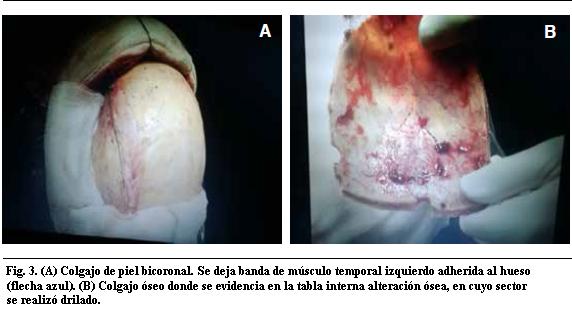

Se realizó tratamiento quirúrgico por abordaje bicoronal con exposición del seno longitudinal superior. Se hizo una exéresis tumoral macroscópicamente completa con plastia de duramadre (Figuras 3, 4 y 5).